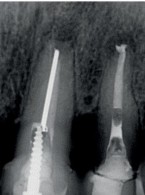

SPECJALISTA RADZI: Nieskuteczna apikotomia wierzchołka korzenia – ponowna resekcja czy powtórne leczenie kanałowe?

Zgłosiła się do mnie 60-letnia pacjentka z nieszczelną i nieestetyczną koroną protetyczną osadzoną na zębie siecznym szczęki. Pacjentka poinformowała, iż ząb był poddany przed laty zabiegowi resekcji. Wykonane zdjęcie potwierdziło wcześniej wykonaną apikotomię oraz obecność niewielkich zmian zapalnych w tkankach okołowierzchołkowych. W kanale stwierdzono dobrze kontrastujący się ćwiek (prawdopodobnie srebrny); w części koronowej kanału był widoczny krótki indywidualny wkład koronowo korzeniowy. Co mogę zasugerować pacjentce? Jakie są możliwości leczenia?